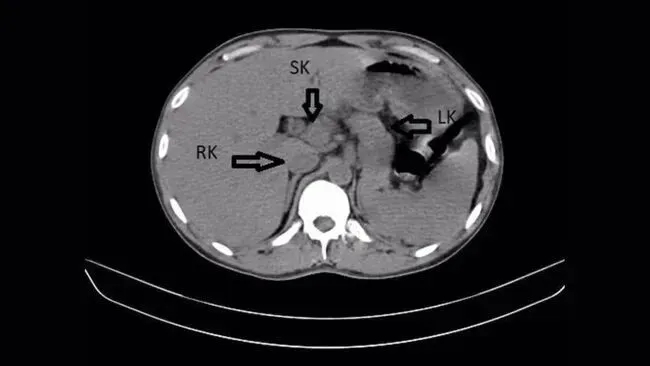

Qua siêu âm bụng và chụp CT, các bác sĩ phát hiện bệnh nhân có quả thận thứ ba, còn được gọi là "thận thừa". Quả thận thừa này nằm ở bên phải và được nối với quả thận phải ban đầu, tạo thành cấu trúc tổng thể hình móng ngựa.

Tuy nhiên, sự hiện diện của một quả thận phụ có thể làm tăng nguy cơ biến chứng đường tiết niệu trong một số trường hợp nhất định. Trong trường hợp này, các nghiên cứu hình ảnh cho thấy cả hai thận đều bị sưng, kèm theo hình thành sỏi. Sỏi thận là những cấu trúc tinh thể được hình thành khi nồng độ khoáng chất trong nước tiểu tăng cao. Sỏi nhỏ thường được đào thải qua nước tiểu, nhưng nếu chúng vẫn còn trong thận hoặc niệu quản, chúng có thể gây tắc nghẽn và thúc đẩy nhiễm trùng.

Trong trường hợp này, nhiễm trùng thận trái của bệnh nhân nghiêm trọng hơn, và có sự tích tụ sỏi trong niệu quản nối thận trái với bàng quang, cho thấy sự tắc nghẽn đường tiết niệu. Tắc nghẽn đường tiết niệu .Điều này có thể dẫn đến ứ đọng nước tiểu, tạo môi trường thuận lợi cho sự phát triển của vi khuẩn. Tình trạng "tắc nghẽn và nhiễm trùng chồng chéo" này được coi là yếu tố chính làm tình trạng bệnh nhân xấu đi. Cần lưu ý rằng thận phụ thường không trực tiếp gây ra nhiễm trùng đường tiết niệu, nhưng các bất thường về mặt giải phẫu đi kèm, chẳng hạn như khả năng thoát nước tiểu kém, có thể làm tăng nguy cơ sỏi và tắc nghẽn đường tiết niệu, từ đó tạo điều kiện cho vi khuẩn phát triển. Trong trường hợp này, sỏi và tắc nghẽn nhiều khả năng là nguyên nhân trực tiếp làm tình trạng nhiễm trùng xấu đi, trong khi thận phụ chỉ là một yếu tố tiềm ẩn.